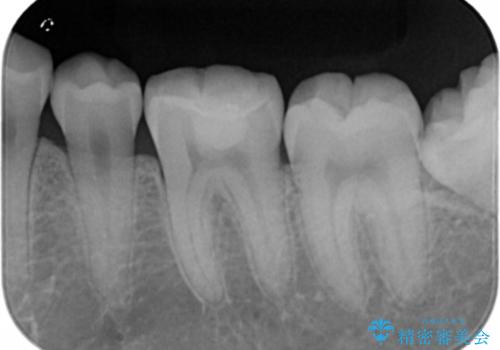

- 10年以上ぶりに歯科に来院された患者です。

口腔内・レントゲン写真からう蝕が見られたので治療を勧めたところ、自費治療を希望されたのでセラミックインレーにて治療を行いました。

左下6番のカリエス除去を行ったところ、深くまで削る必要があったため、CR裏層をした上でセラミックインレー形成をしました。